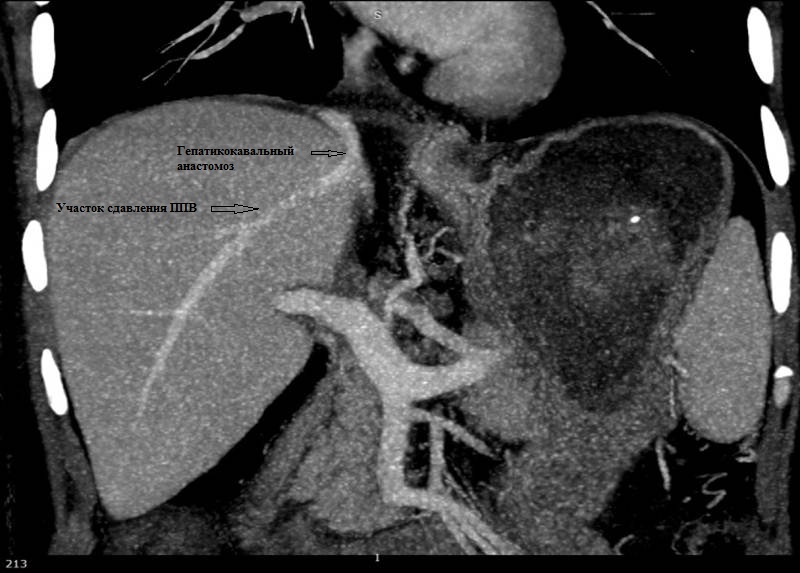

17. Рис. 9а Стеноз ППВ, гипертрофированным трансплантатом | |

18. Рис.9б Состояние после стентирования ППВ | |